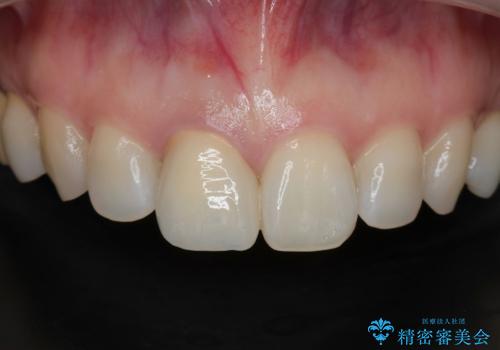

問題なく綺麗な被せ物が入りました。

保険の被せ物は安価ですが劣化しやすいため着色しやすい素材です。

セラミックの素材は劣化することなくまた虫歯の再発のリスクも下げてくれます。